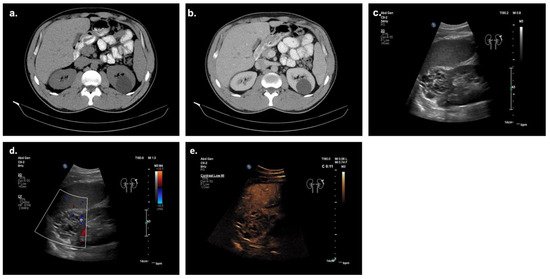

Show Figures